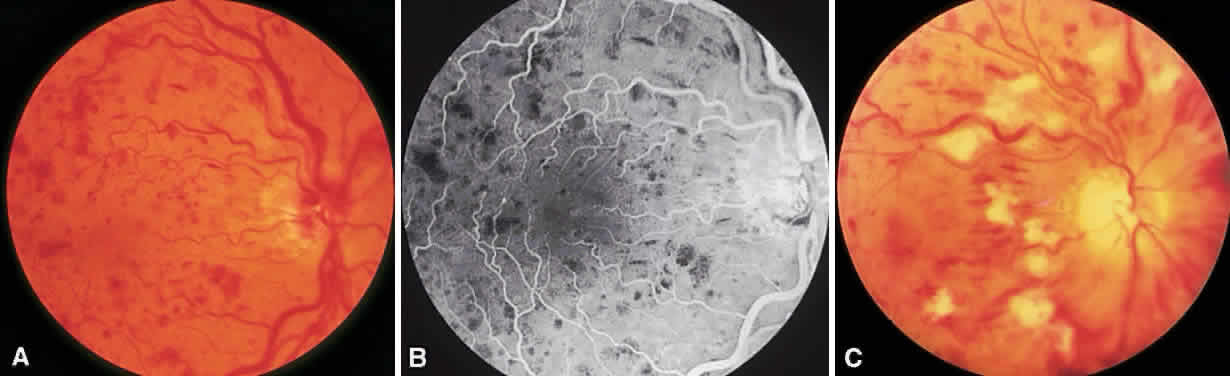

In the DRS, certain high-risk characteristics (HRCs) were identified as being the most accurate prognostic indicators of visual loss. HRCs include neovascularization on or within one disc diameter of the disc (NVD) that is equal to or greater than one fourth to one third of the disc area in extent or any NVD or retinal neovascularization else-where (NVE) associated with preretinal or vitreoushemorrhage (Fig. 1B). For eyes with these clinicalcharacteristics, prompt PRP is recommended. Forpatients with severe or severe nonproliferativediabetic retinopathy (NPDR), as well as for patientsin whom adequate follow-up cannot be ensured, early scatter therapy may be considered.26 The presence of rubeosis iridis or neovascular glaucoma in the setting of PDR, even without HRCs, may warrant PRP.27–29

To complete scatter treatment, burns should be applied to the retina beginning at points on an oval defined as two disc diameters above, below, and temporal to the center of the macula, and one disc diameter nasal to the disc, and should extend peripherally at least to the equator (Fig. 2). This approach may help avoid inadvertent macular burns. A report by Blankenship suggests that sparing of the posterior aspect of the fundus may be possible without diminishing the beneficial effects of treatment.31 With the Goldmann lens, a 500-μm spot size is used, whereas with the panfunduscopic lens, a 200-μm spot is used. When vitreous hemorrhage is present, it may be necessary to reduce the size of the spot to 200 μm or to use a krypton or diode laser rather than an argon laser. The Krypton Argon Regression of Neovascularization Study found that krypton and argon were equally effective in inducing regression of NVD.32